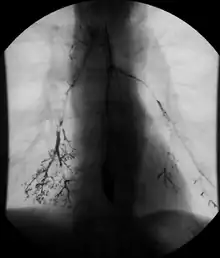

Enteroclysis

In addition to fasting for 8 hours prior to examination, a laxative may also be necessary for bowel preparation and cleansing.[12] The main aim of this study is to distend the proximal bowel through infusion of large amount of barium suspension. Otherwise, the distension of distal small bowel is generally similar with small bowel follow-through. Therefore, there is a need to pass a tube through the nose into the jejunum (nasojejunal tube) to administer large amount of contrast. This can be unpleasant to the subject, requires more staff, longer procedural time, and higher radiation dose when compared to small bowel follow-through. The indications for enteroclysis are generally similar to small bowel follow-through. Barium suspensions such as diluted E-Z Paque 70% and Baritop 100% can be used. After that, 600 ml of 0.5% methylcellulose is administered after 500 ml of 70% barium suspension is given. Bilbao-Dotter tube and Silk tube can be used to administer barium suspension. The subject should be fasted overnight, any antispasmodic drugs should be stopped one day before the examination, and Tetracaine lozenges can be used 30 minutes before the procedure to numb the throat for nasojejunal tube insertion.[13]

The filling of the small intestines can be viewed continuously using fluoroscopy, or viewed as standard radiographs taken at frequent intervals. The technique is a double-contrast procedure that allows detailed imaging of the entire small intestine. However, the procedure may take 6 hours or longer to complete and is quite uncomfortable to undergo.[23]